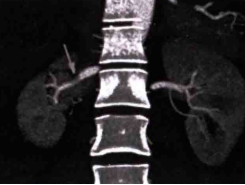

患者于2021年7月29日接受右肾动脉血管扩张成形术。术后逐步停用降压药及补钾药物,短期内在当地医院多次随访血压维持在正常范围。随访情况:术后3个月,血压再次升高,波动于(140~150)/(90~100) mmHg,但多次复查血钾均正常。术后半年门诊复查肾CTA(图3):右肾动脉局部仍存在轻度狭窄,走行较纤细,较术前已明显好转。非卧位2h醛固酮91.32 ng/dl,肾素浓度69.58 ng/L。嘱患者口服钙离子拮抗剂类药物控制血压。术后1年门诊复查肾CTA(图4):右肾动脉狭窄程度大致同前,未进一步加重。血压维持在(120~130)/(90~100) mmHg,多次复查血钾及肾功能均正常。

图3. 术后半年复查肾CTA